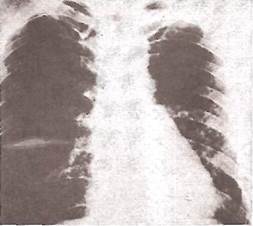

Рис. 25. Рентгенограмма легких больного с правосторонним экссудативным плевритом